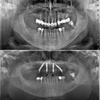

Implant Treatment